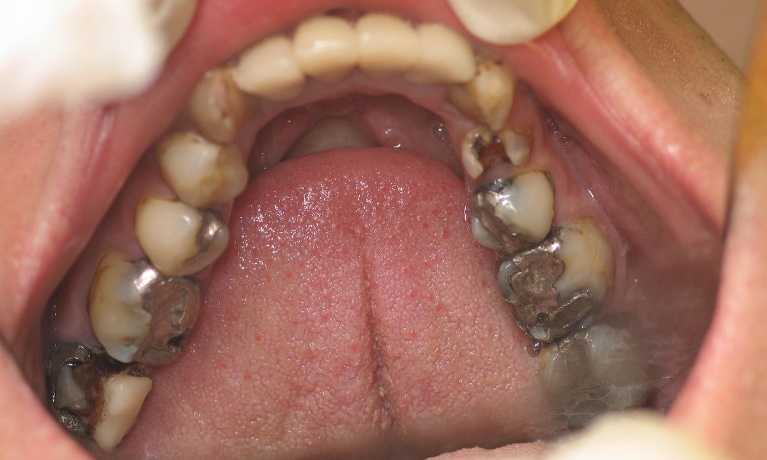

Smile Gallery

Are you considering dentistry at Michael J Nelson DDS? If so, we’d like to invite you to browse our Smile Gallery. Our dental team can improve your oral health and help you attain the attractive smile you’ve always wanted.